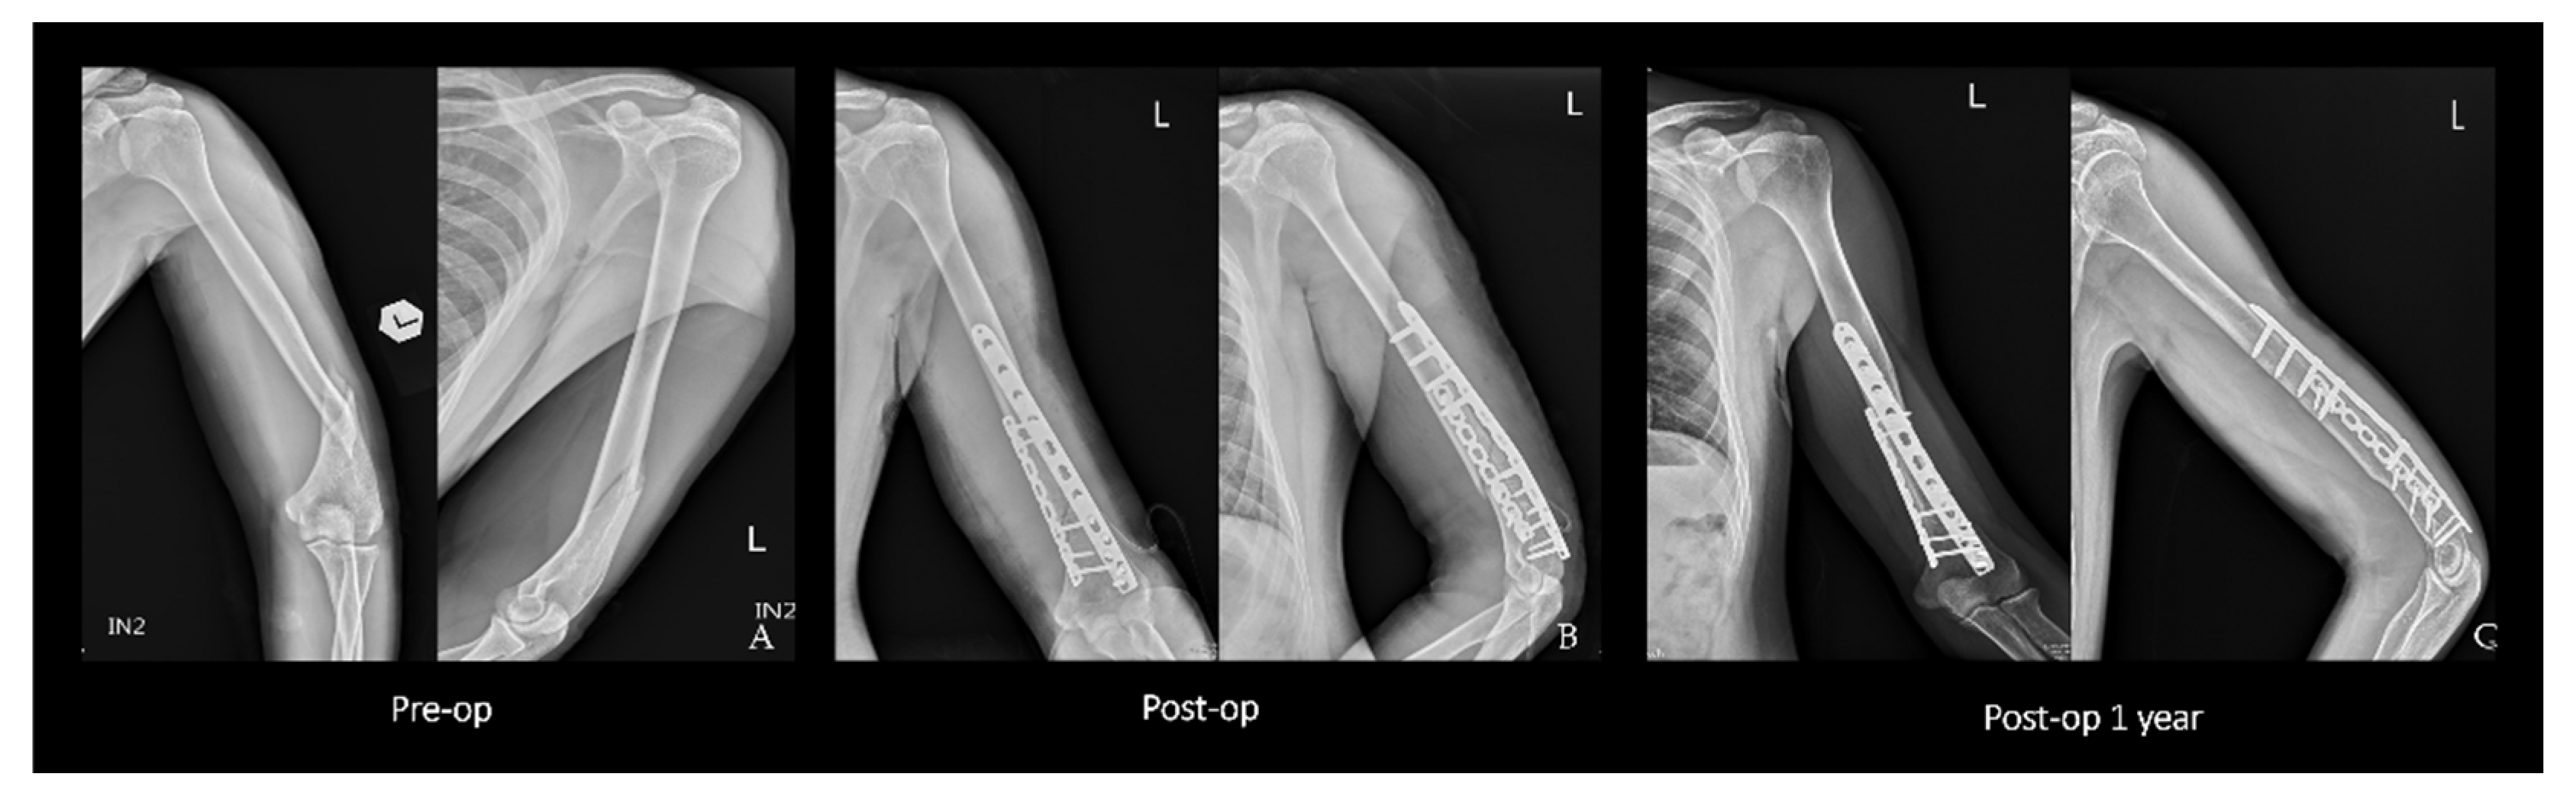

2.2. Surgical Technique

2.3. Double Plating

2.4. Single Plating